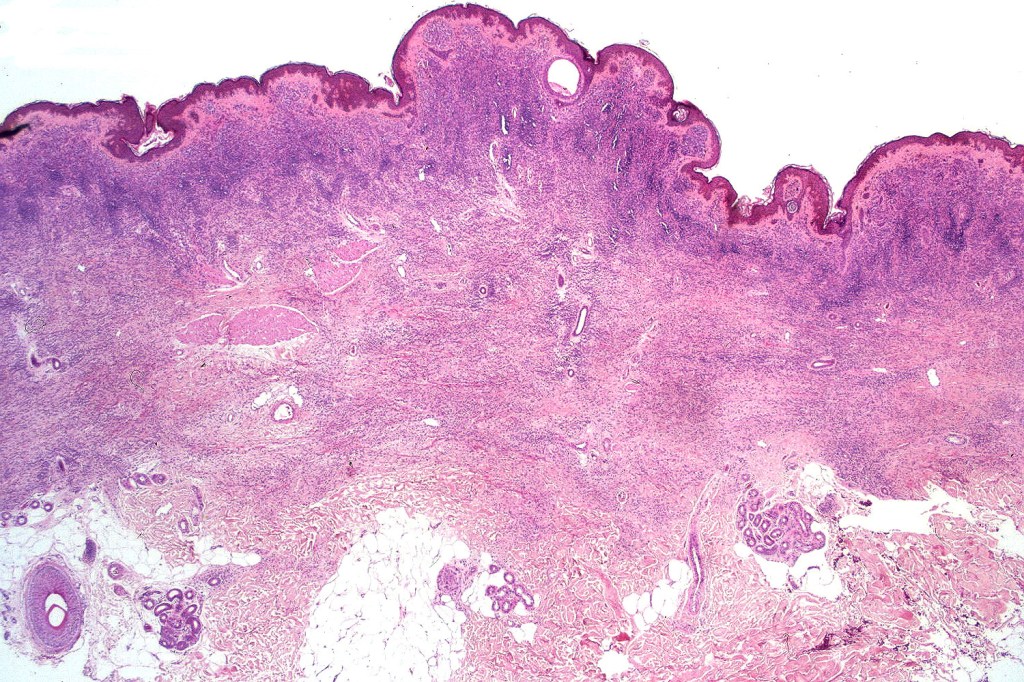

Histological features

•Most often are distinctive at scanning/low power examination due to the depth of involvement

•Hyperkeratosis, acanthosis and commonly papillomatosis

•Nested junctional component & nests within the papillary dermis

•Diffuse infiltrate of nevus cells often extending deeply into the dermis or beyond, single filing is often present at base & may involve the septa of the subcutaneous fat

•Involvement of appendages & arrector pili muscles